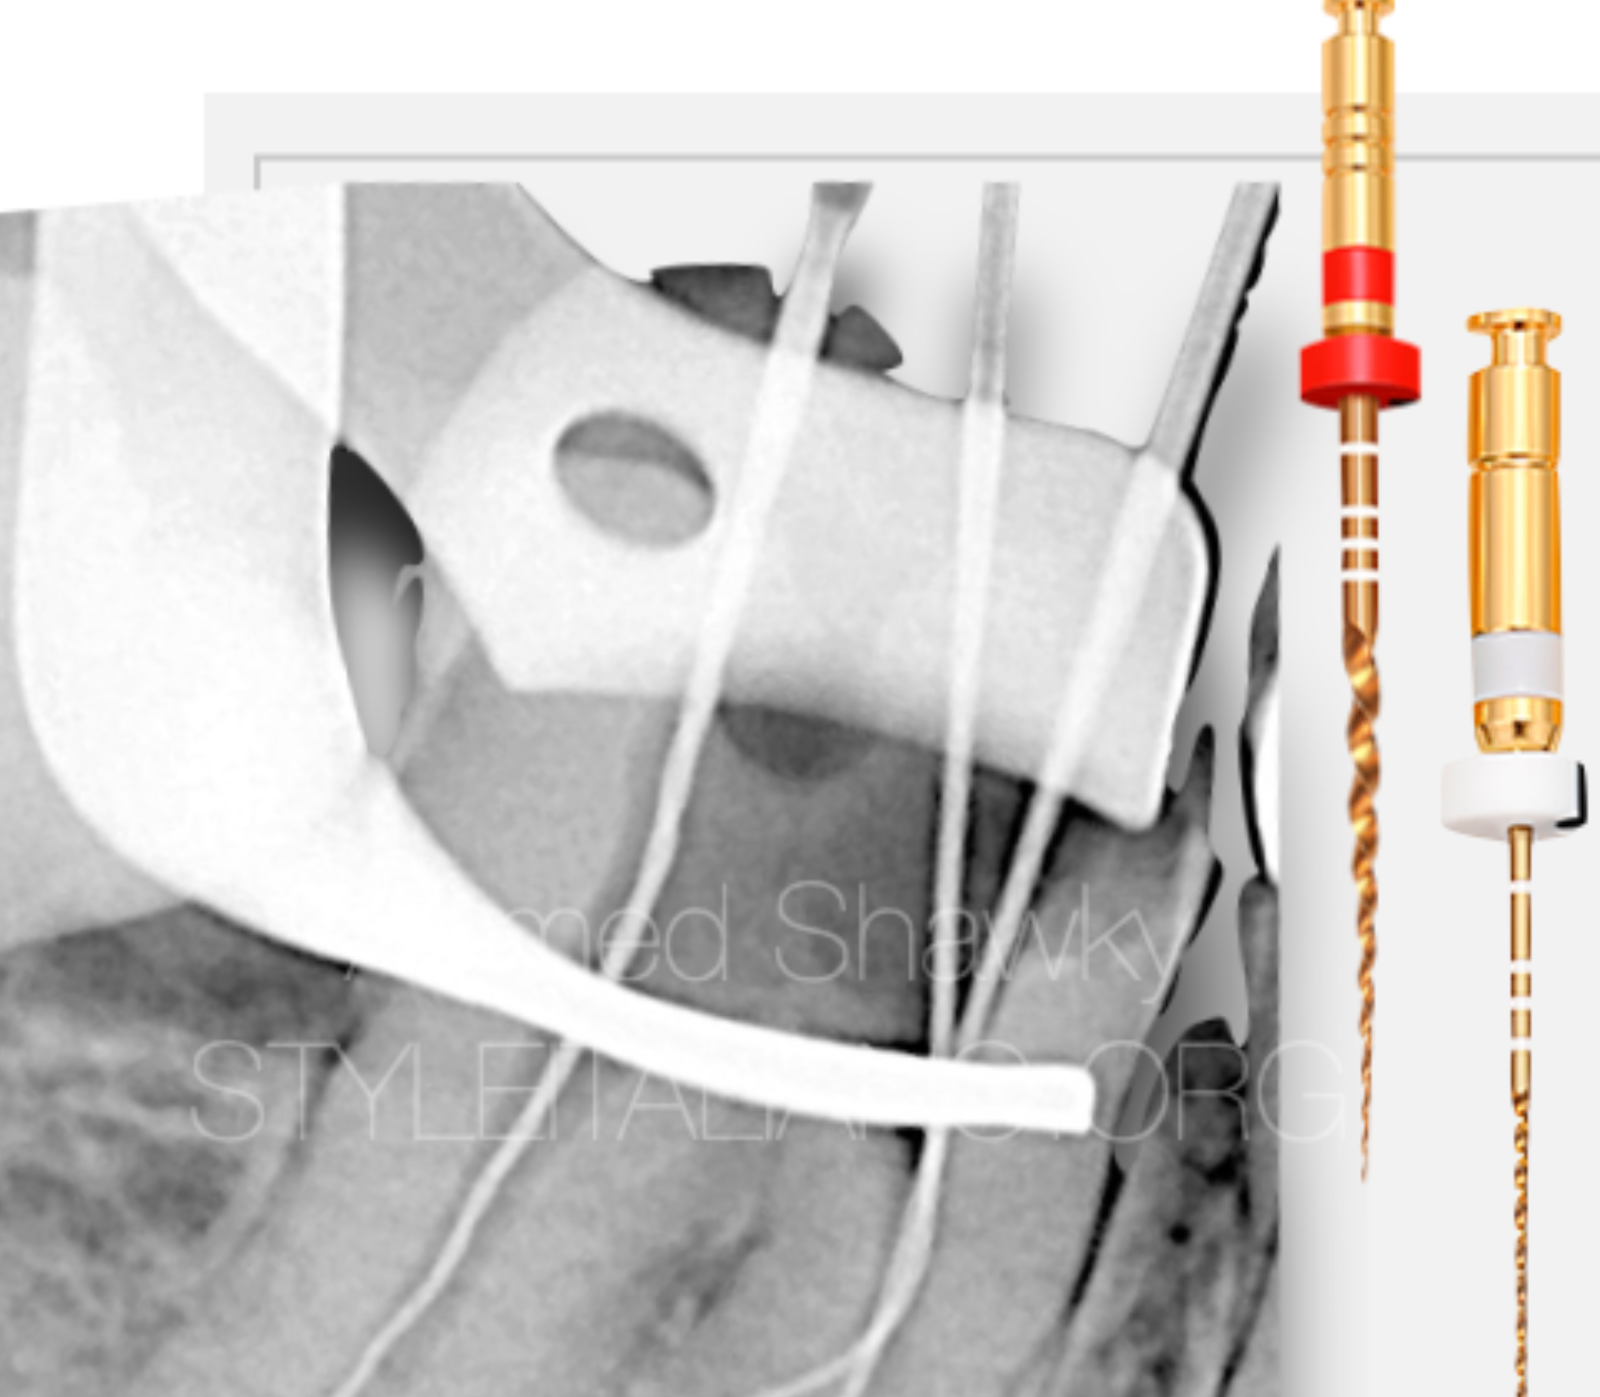

Treatment was performed over two visit, where the first visit was dedicated to retrieval of the separated instrument using loop technique.

Briefly, management of the separated instrument involved the use of thin ultrasonic tips operated on low power setting, to avoid any possible secondary fracture of the small size, yet long fragment, considering minimal loss of dentin during retrieval.

Shaping of the mesial root canal system was performed, combining two different alloys and two different kinematics;

The MG3 Gold Instruments, [25/.06, & 20/.06] were used in the coronal portion of the root canal, “on two levels” to benefit from the cutting efficiency during mechanical pre-flaring. These instruments were used in ATR mode “adaptive motion” in a BR Rap motor, to adapt the instrument to the condition of the canal in that portion.

Patency was achieved using K files after coronal pre-flaring Followed by Mechanical Glide path using MG3 Gold 15/.03